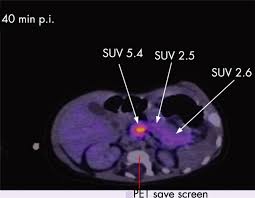

An F-DOPA PET scan is a specialized imaging test designed to study dopamine activity in the brain. It plays a crucial role in diagnosing conditions such as Parkinson’s disease, movement disorders, certain neuroendocrine tumors, and complex neurological symptoms. The reason many people look for Affordable F-DOPA PET Scan Services is because the tracer used—called F-18 DOPA—is highly specialized, and the process requires advanced nuclear medicine technology.

Affordability should never mean outdated technology. The best centers offering Affordable F-DOPA PET Scan Services use modern high-resolution PET CT scanners that deliver clear, accurate images.